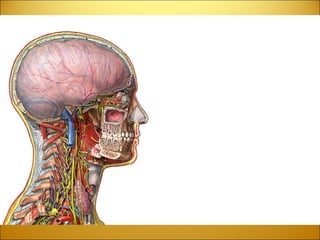

Divisions of the Brain FOREBRAIN (PROSENCEPHALON) TELENCEPHALON DIENCEPHALON MIDBRAIN (MESENCEPHALON) MESENCEPHALON HINDBRAIN (RHOMBENCEPHALON) ) METENCEPHALON MYELENCEPHALON

TELENCEPHALON Cerebral Hemispheres Function :   Determines Intelligence  Personality  Interpretation of Sensory Impulses  Motor Function  Planning and Organization  Touch Sensation  Location :   The cerebrum is located in the anterior portion of the forebrain.  It is divided into two hemispheres that are connected by the corpus callosum.

DIENCEPHALON Function :   Chewing  Directs Sense Impulses Throughout the Body  Equilibrium  Eye Movement, Vision  Facial Sensation  Hearing  Phonation  Respiration  Salivation, Swallowing  Smell, Taste   Location :   The diencephalon is located between the cerebral hemispheres and above the midbrain Structures :   Structures of the diencephalon include  the thalamus, hypothalamus, the optic tracts, optic chiasma, infundibulum, 3 rd  Ventricle, mammillary bodies, posterior pituitary gland and the pineal gland.

DIENCEPHALON The  thalamus  is a major relay center to the cortex for all sensations (sight, etc) except for smell.  The  hypothalamus  controls many functions including hunger, thirst, pain, pleasure and the sex drive.  Another key function of the hypothalamus is to regulate the pituitary gland, which in turn, regulates hormonal levels in the body.

MESENCEPHALON Midbrain Function :   Controls Responses to Sight  Eye Movement  Pupil Dilation  Body Movement  Hearing  Location :   The mesencephalon is the most rostral portion of the brainstem. It is located between the forebrain and brainstem.   Structures:   The mesencephalon consists of the tectum and tegmentum.

METENCEPHALON Pons Function:   Arousal  Assists in Controlling Autonomic Functions  Relays Sensory Information Between the Cerebrum and Cerebellum  Sleep   Location:   The pons is the portion of the brainstem that is between the midbrain and the medulla oblongata.

METENCEPHALON Cerebellum Function :   Controls Fine Movement Coordination  Balance and Equilibrium  Muscle Tone  Location :   The cerebellum is located just above the brainstem, beneath the occipital lobes at the base of the skull.

MYELENCEPHALON Medulla Oblongata Function:   Controls Autonomic Functions  Relays Nerve Signals Between the Brain and Spinal Cord  Location:   The medulla oblongata is the lower portion of the brainstem. It is inferior to the pons and anterior to the cerebellum.

Brainstem Function:   Alertness  Arousal  Breathing  Blood Pressure  Contains Most of the Crainal Nerves  Digestion  Heart Rate  Other Autonomic Functions  Relays Information Between the Peripheral Nerves and Spinal Cord to the Upper Parts of the Brain   Location:   The brainstem is located at the juncture of the cerebrum and the spinal column. It consists of  the midbrain, the pons and the medulla oblongata.